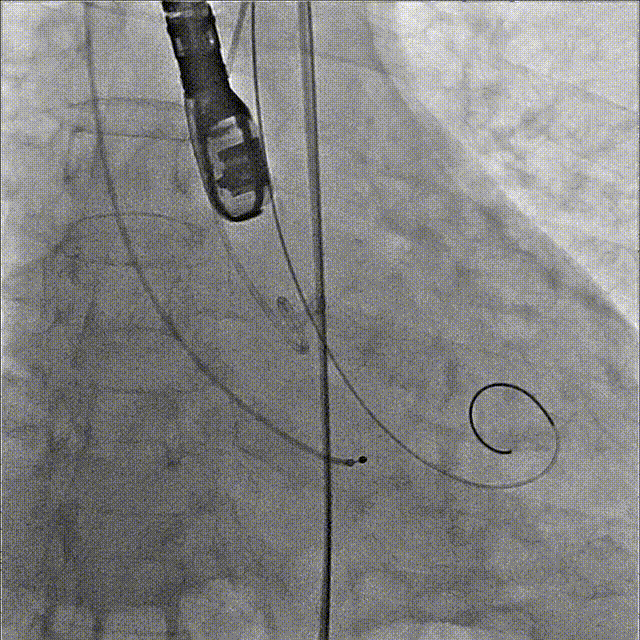

3、交换加硬导丝super stiff至心室;

4、通过14F E-sheath大鞘,送入23mm SAPIEN3瓣膜,利用Commander输送系统独特调弯功能,顺利过弓;

5、调整至共平面角度,在加硬导丝支撑下,成功跨瓣;